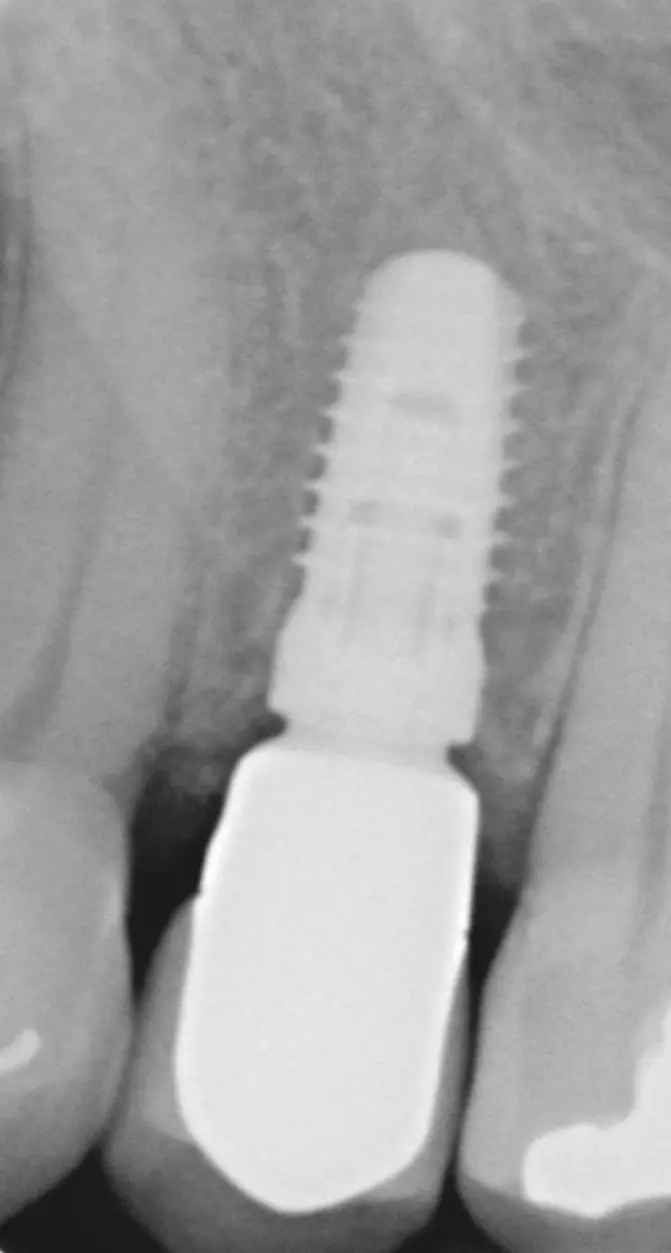

Der Emergenzwinkel ist definiert als der Winkel, der sich aus der Schleimhaut zugewandten Abutmentoberfläche und der Implantatlängsachse ergibt (Abb. 1). Das Emergenzprofil ist definiert als die Kontur des der Mukosa zugewandten Abutmentanteils (Abb. 2).

Bone-Level Implantate zeigten ein signifikant höheres Periimplantitisrisiko, wenn der Emergenzwinkel >30° betrug, im Vergleich zu den Bone-Level Implantaten, deren Abutment ein Emergenzwinkel von <30° aufwies (31,3% zu 15,1%). Bei Tissue-Level Implantaten konnte dieser Zusammenhang nicht nachgewiesen werden.

Wenn zusätzlich zu dem Emergenzwinkel auch noch das Emergenzprofil in die Analyse einbezogen wurde, zeigte sich bei einem Emergenzwinkel >30° in Kombination mit einem konvexen Emergenzprofil (Abb. 3) auf mindestens einer interproximalen Seite eine signifikante Erhöhung der Periimplantitisprävalenz von 37,8% (p=0,003).

Auch diese signifikante Erhöhung des Periimplantitisrisikos bezieht sich auf Bone-Level Implantate, nicht aber auf Tissue-Level Implantate. Es scheint, dass die reduzierte Hygienefähigkeit und die damit verbundene erhöhte Plaqueakkumulation für die erhöhte Periimplantitisprävalenz von Implantaten, die mit Abutments mit weitem Emergenzwinkel und konvexem Emergenzprofil versorgt sind, verantwortlich sind [11].

Der in Abbildung 4 gezeigte Emergenzwinkel und Emergenzprofil ist zum einen der Weichgewebshöhe als auch der Implantatposition geschuldet. Bei solchen Situationen, die häufig im Unterkierferseitenzahnbereich auftreten, muss sich der Chirurg vor der Implantation folgende Gedanken machen: